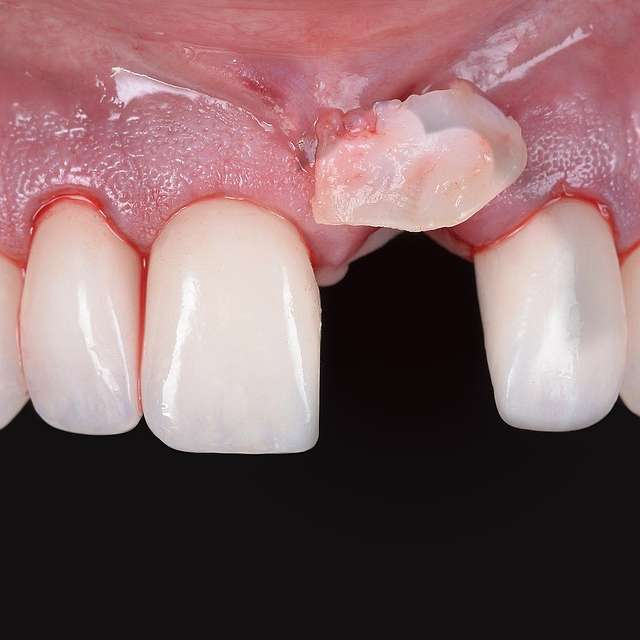

A gingival graft is a micro-surgery that will transplant a bulk of soft tissue - free gingiva or connective tissue ( the internal layer of gingiva ) to cover a soft tissue defect. Usually this type of procedures is required to augment implants, or to cover defects caused by periodontal disease or trauma. The grafts are harvested from the third molar region or the palate, and are transported where they are needed.

This type of procedure is a very delicate one, using the same type of blades like the ones used in ophthalmology and the sutures are also very thin. The sutures will be removed after 7-14 days, depending on the case, when primary healing is achieved. The maturation of the graft will take roughly 90 days, this is the reason why, when placing implants we prefer to also do the graft, so we can sync the healing time for both procedures.

Using tissue grafts to correct tissue defects

Using tissue grafts to correct gingival levels or cover recessions